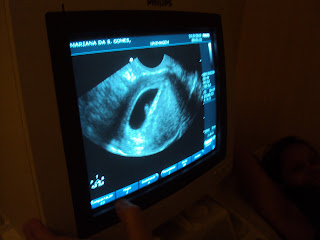

A mamãe tem enjoado bastante! Mas as náuseas e os vômitos durante as primeiras semanas da gravidez são normais e até um sinal de que tudo comigo vai bem!Por falar nisso, hoje estou com 8 semanas e 4 dias. E continuo me desenvolvendo super bem!